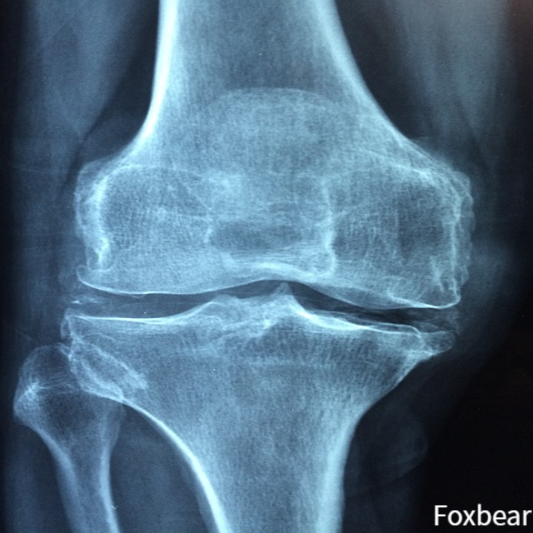

관절 건강: MSM은 관절 건강에 효능이 있다고 가장 일반적으로 알려져 있습니다. 서두에서 말씀드렸듯 MSM은 피크노제놀과 보스웰리아 영양소와 함께 관절의 통증과 기능 모두에 효과가 좋다고 연구 결과가 나왔습니다.